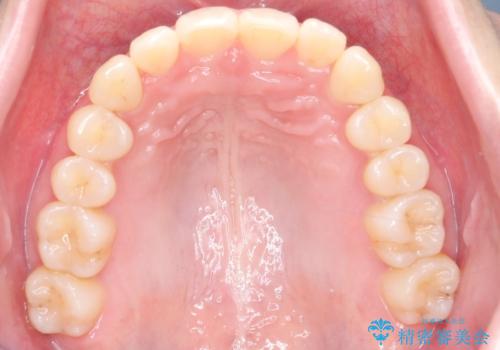

インビザライン矯正|下顎前歯1本抜歯でスムーズに歯列改善(1年で完了)

- 患者様は、下顎前歯のガタつきを改善したいとのことで来院されました。診察の結果、スペース不足により前歯が重なっている状態でした。抜歯をせずに並べると前歯が前方に突出してしまうため、下顎の前歯を1本抜歯し、インビザラインで矯正する治療計画を立てました。できる限り追加のアライナーを使用せずに治療を完了できるよう、初回の治療計画を慎重に設計しました。

下顎前歯を1本抜歯し、歯列のスペースを確保。その後、インビザラインを用いて計画通りに歯を移動させ、噛み合わせも整えました。患者様の協力もあり、ゴムかけなどを適切に行い、予定通り1年で治療を完了。追加アライナーを使用することなく、計画通りに治療を終えることができました。患者様からは「思ったより早く終わり、仕上がりにも満足している」と喜びの声をいただきました。